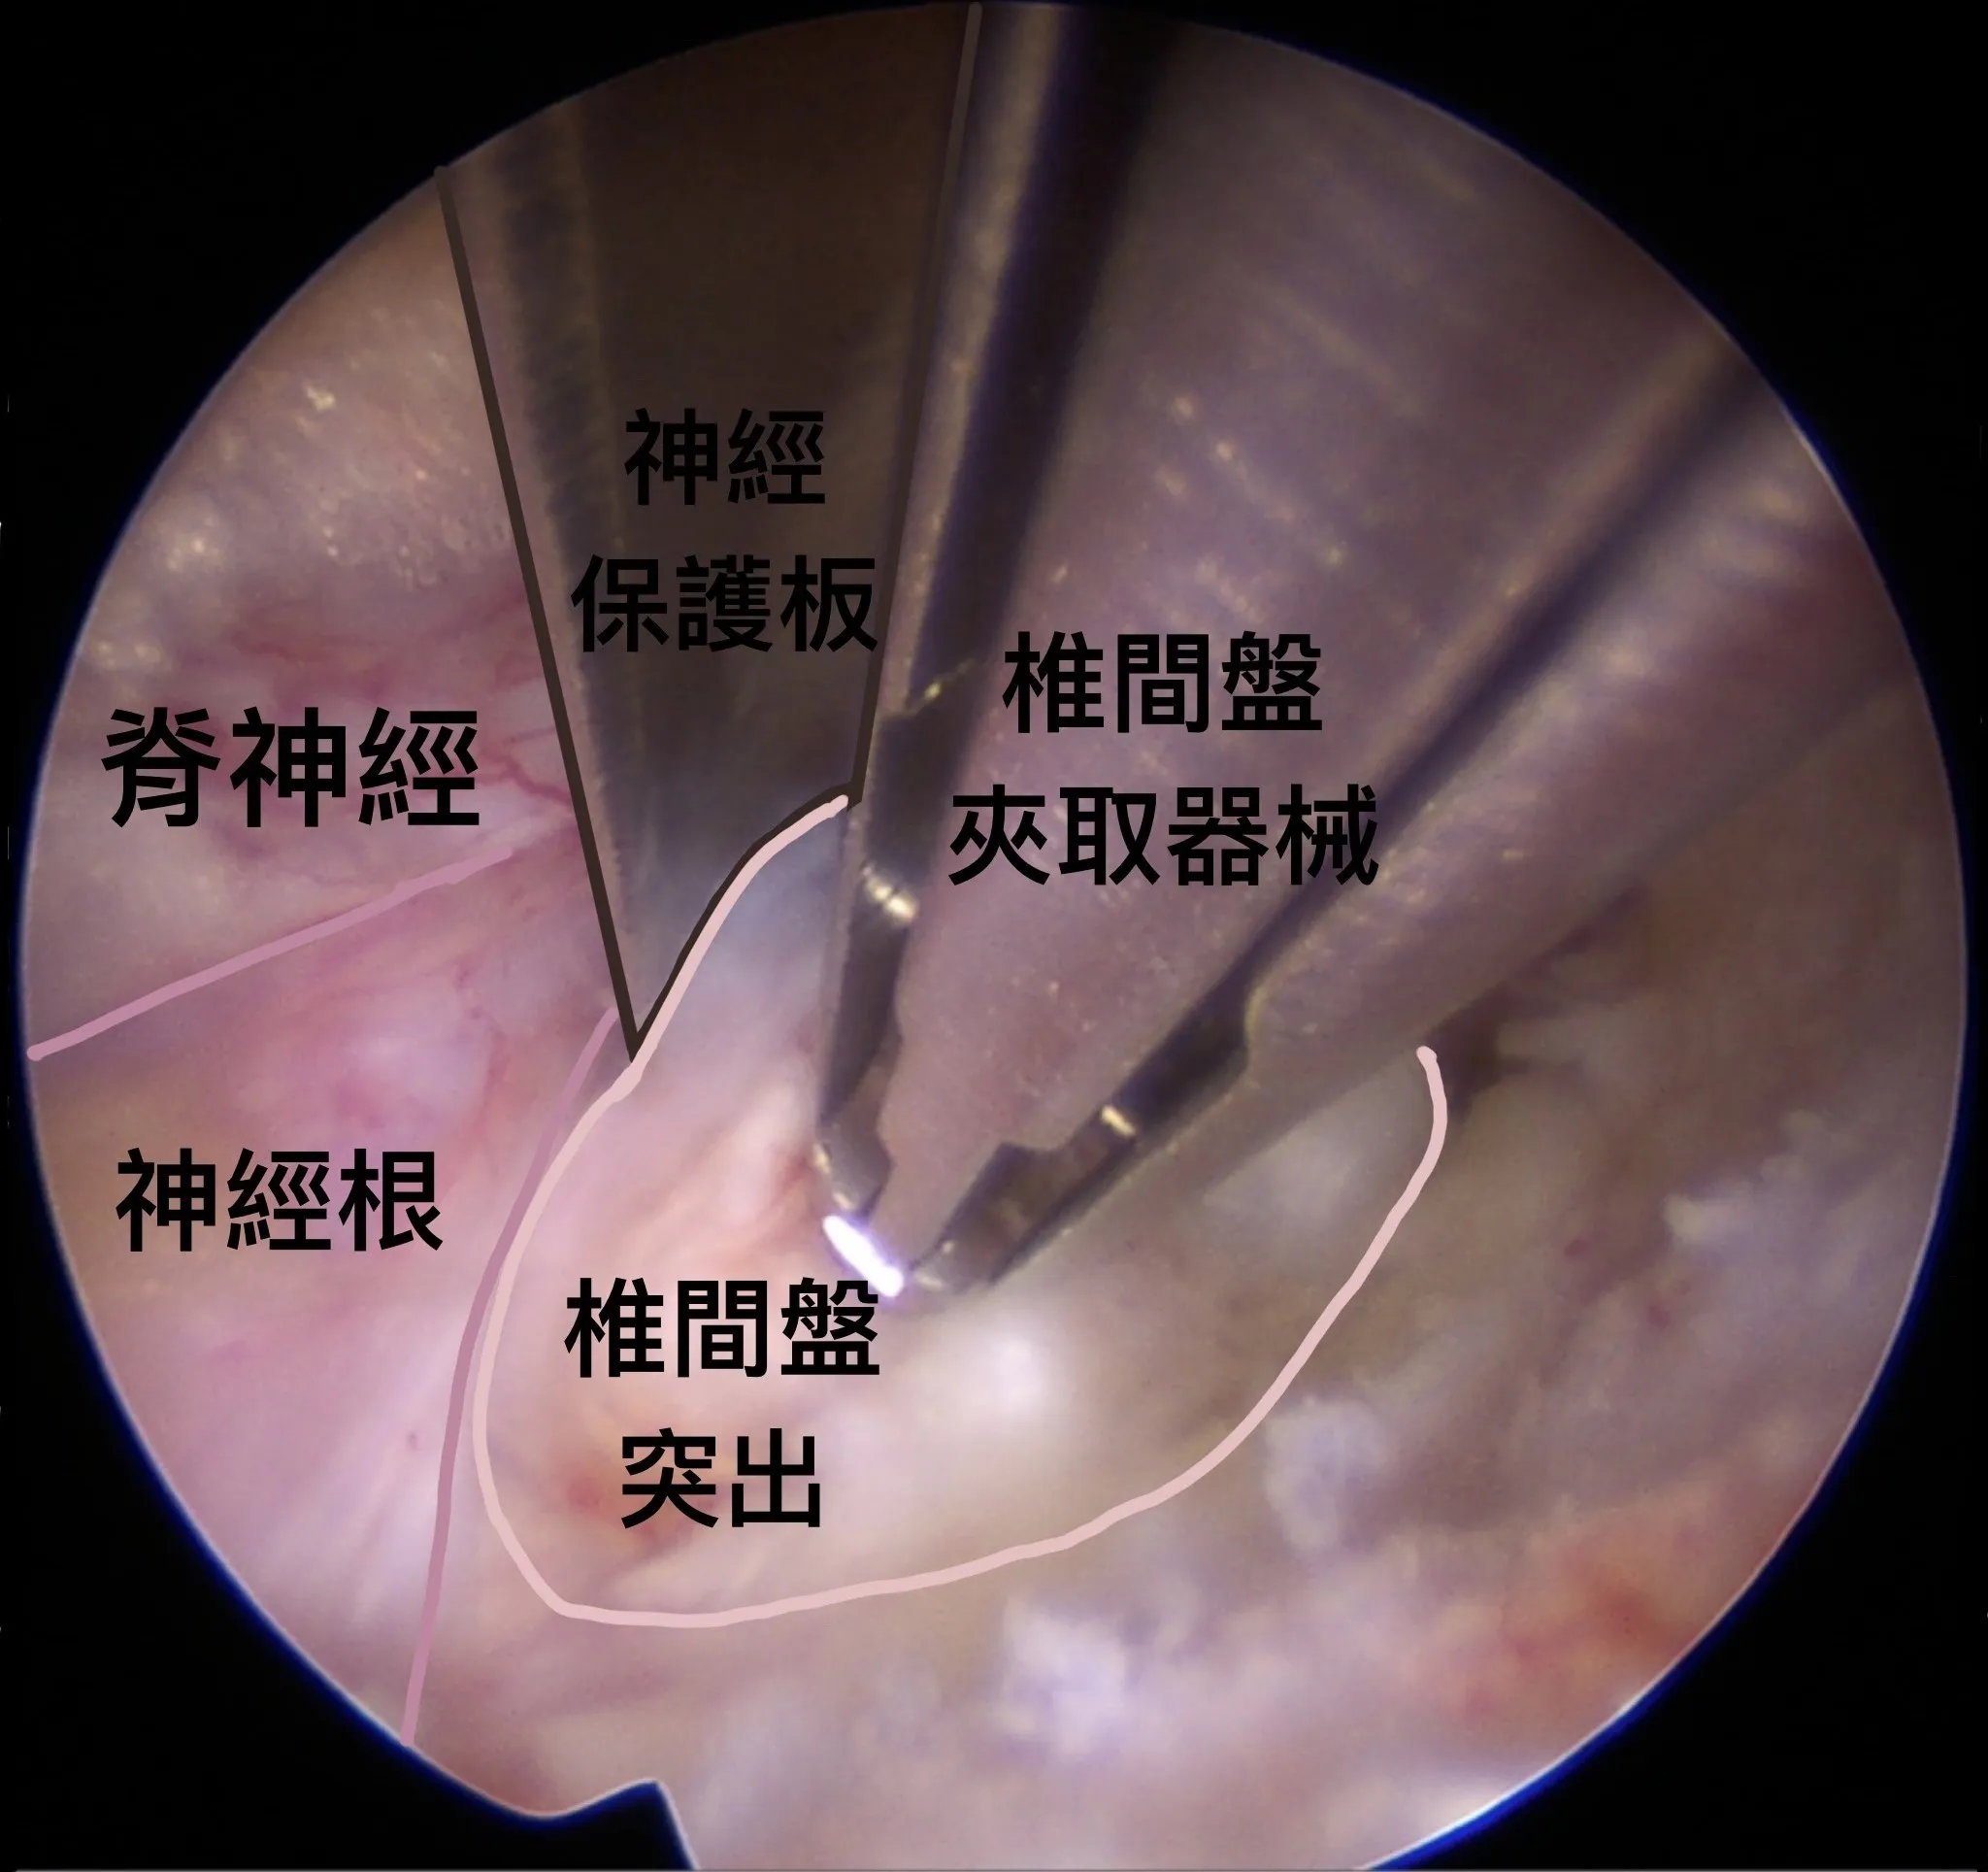

使用神經保護板把神經根撥到旁邊,才不會被夾取器械誤傷;突出的椎間盤則慢慢地被清除。

脊椎內視鏡手術的優點在於能以不到一公分的小傷口,透過高解析度內視鏡深入病灶,清楚的在神經之間將椎間盤突出分離並完全切除。喻醫師表示,神經很常因為嚴重發炎而與突出的椎間盤產生沾黏,傳統手術因視野受限,容易傷及神經或未能完全清除病灶,而內視鏡技術可以放大病灶細節,讓手術能更加精準和安全。